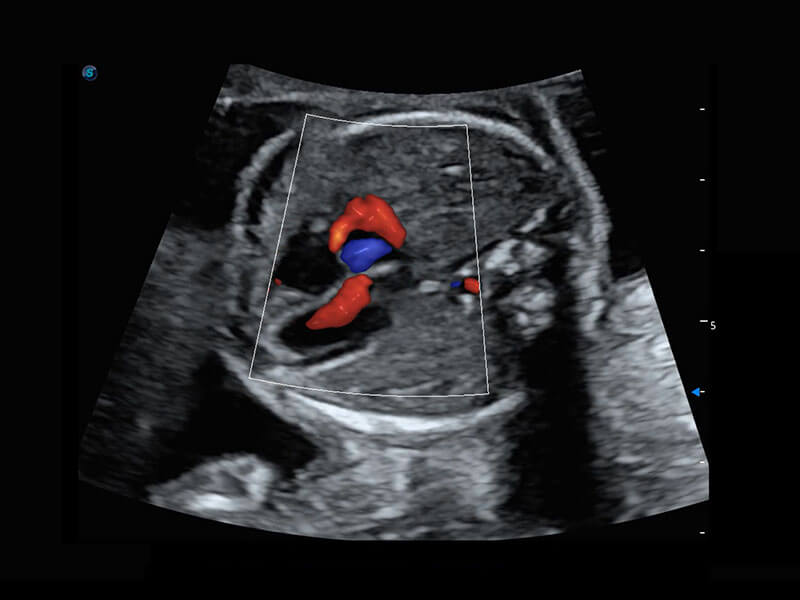

右室双出口

胎心容积成像